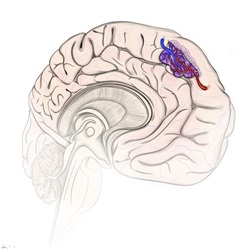

Cavernous malformations, or cavernomas, are abnormal clusters of blood vessels that can be found anywhere in the body but usually only poses a serious problem in the brain and spinal cord.

In some patients, cavernous malformations may exist without any symptoms. However, in other people, these masses may bleed causing neurological issues, such as seizures and stroke-like deficits, which in some cases can be life-threatening.

Cavernous malformations may be treated surgically to remove these risks.